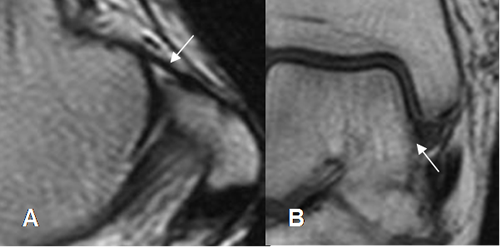

Fig 17. Ligamento calcaneoescafoideo.

A: RM axial en T1 y B: RM sagital en T2. Ligamento hipointenso normal, entre el escafoides y el calcáneo.